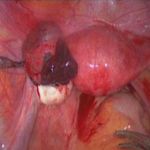

陈凤林教授指出:北京安太医院治疗宫外孕可进行3D腔镜下开窗取胚,宫外宫内转移,继续妊娠.不切输卵管,同时寻找病因去除之!